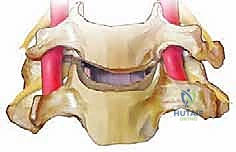

الخطوة 6: زراعة الطعم العظمي (Bone Graft Insertion)

بعد إزالة القرص، تتبقى فجوة بين الفقرتين. لمنع انهيار هذه المسافة ولتحفيز التحام الفقرتين معاً، يتم إدخال "طعم عظمي" أو قفص صناعي (Cage) مصنوع من مادة PEEK أو التيتانيوم ومملوء بمادة عظمية.

الخطوة 7: التثبيت المعدني (Instrumentation)

لضمان الاستقرار الفوري ومنع حركة الطعم العظمي حتى يكتمل الالتحام (والذي يستغرق أشهراً)، يقوم الدكتور هطيف بتثبيت شريحة معدنية صغيرة من التيتانيوم على الجزء الأمامي من الفقرتين باستخدام براغي دقيقة.